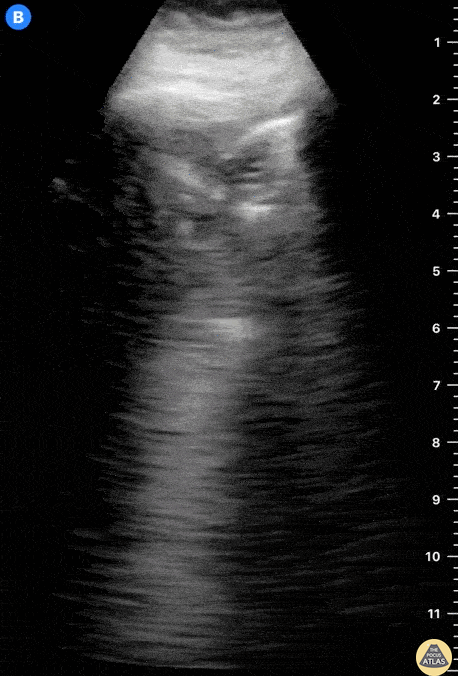

A 22-year-old patient without a medical background presents to the ED with a 2-day history of left costal stabbing pain. There was no shortness of breath nor fever and barely any respiratory symptoms. Lung ultrasound revealed a thick, interrupted pleural line and a mobile, hypoechoic structure with irregular edges compatible with a consolidation. Covid PCR was negative. Dr. Felipe Urriola P.